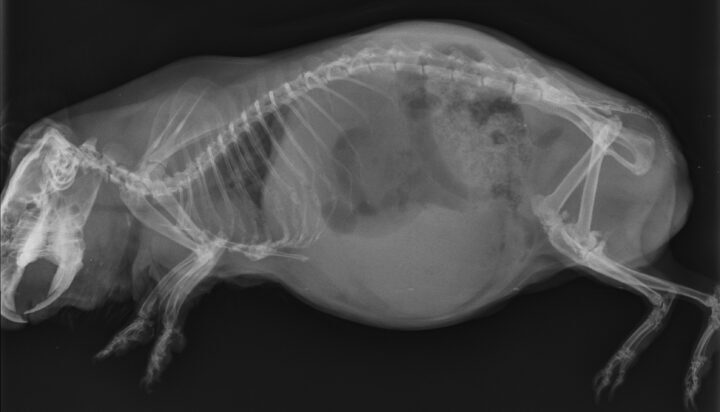

Often, clinical signs are missed, and the diagnosis in guinea pigs is made during post-mortem examination (DeCubellis and Graham, 2013). However, when present, clinical signs can range from anorexia, lethargy, tachypnoea, an absence of faecal production, cyanosis and cardiovascular shock to sudden death (DeCubellis and Graham, 2013; Edis, 2019). Patients can be presented obtunded, with palpable gastric tympany and hypothermia (Mitchell et al., 2010). It is important to distinguish this condition from bloat – another common condition in which guinea pigs present with gastric tympany.

GDV is an emergency presentation that must be identified quickly. The gaseous distension of the stomach causes it to twist on its axis at the mesentery, resulting in compression of the gastric vessels and secondary ischaemia (Edis, 2019). Fermentation of ingesta contributes to further gaseous distension in the stomach that cannot escape as the gastric outflow is also obstructed due to the twisting of the stomach.

Diagnosis is often by radiography, which should be performed following administration of analgesia and sedation if required. Radiographs show severe gaseous distension of the stomach, often taking up 50 percent of the abdominal cavity (Huynh and Pignon, 2013). In some cases, the bowel can be visualised cranial to the stomach (Mitchell et al., 2010) (Figure 5). It is important to note that the classic “double bubble” seen in cases of GDV in canine patients is not always seen radiographically, and diagnosis of GDV in guinea pigs should not be ruled out based on the absence of this sign.

Decompression should be attempted by passing a red rubber tube or feeding tube down the oesophagus and into the stomach (DeCubellis and Graham, 2013). If GDV is present, this will likely be difficult or impossible due to the torsion. In these cases, a percutaneous needle trocar can be attempted to relieve the gas; however, this risks gastric or caecal rupture as well as secondary peritonitis (DeCubellis and Graham, 2013), so should only be attempted if completely necessary. Emergency surgery is indicated to correct the volvulus and relieve the gaseous tympany.